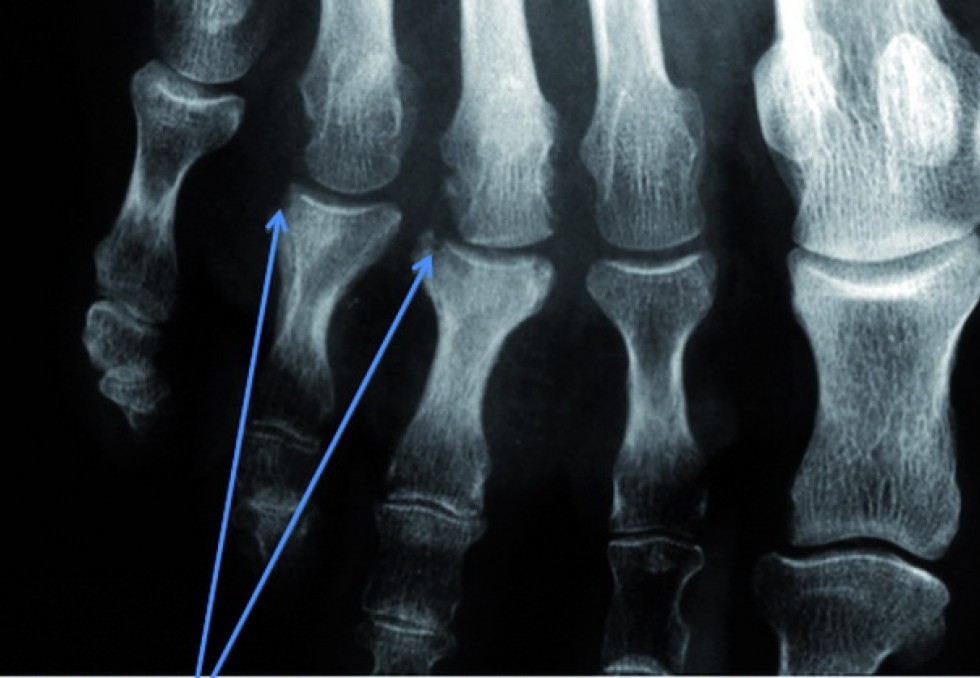

Les patients avec un rhumatisme psoriasique pourraient bénéficier prochainement de nouvelles biothérapies. Après le sécukinumab et l’ixékizumab, de nouveaux anti-IL17 sont ainsi en développement comme le bimékizumab. Cet anticorps monoclonal possède la caractéristique de bloquer les effets à la fois de l’IL17 A et de l’IL17 F, "qui coopèrent de manière indépendante et avec d’autres cytokines pour favoriser l’inflammation", a expliqué le Pr Christopher T. Ritchlin (Université de Rochester, États-Unis). Ce qui laisse espérer une activité plus forte. Un essai de phase 2b, entrepris chez 206 patients a effectivement mis en évidence, avec ce biomédicament, un taux de réponses intéressant (46 % de réponses ACR50 contre 7 % sous placebo après 12 semaines à la dose de 160 mg), "l’efficacité étant observée que les patients aient reçu ou non antérieurement un anti-TNF". Aucun cas de Mici (qui est un effet secondaire suspecté, mais non certain, des anti-IL17) n’a été relevé. Après le tofacitinib, le filgotinib, un inhibiteur sélectif de JAK1, pourrait aussi être utilisé dans le rhumatisme psoriasique, un taux de 80 % de réponses ACR20 (contre 33,3 % sous placebo) ayant été observé après 16 semaines dans l’étude de phase 2 Equator, menée chez 131 patients. Cet anti-JAK a atténué le prurit secondaire au psoriasis cutané associé, "ce qui est important pour les malades", a fait remarquer le Pr Philip J. Mease (Université de Washington, Seattle, États-Unis). Les rhumatologues attendent aussi des progrès thérapeutiques de l’arrivée de biomédicaments ciblant spécifiquement l’IL-23 (et dirigés contre l’IL-23p19), alors que l’on ne disposait jusqu’ici que de l’ustékinumab, un anti-IL23p40 également actif sur l’IL12. De fait, un anti-IL23p19, le tildrakizumab, a permis d’obtenir, dans un essai de phase 2b, mené chez 391 patients, une activité notable "se manifestant dès la 8e semaine", a rapporté le Pr Mease (taux de réponses ACR 20 et ACR 50 autour de respectivement 80 % et 50 % à 24 semaines).  Les années qui viennent permettront de mieux évaluer les effets des différentes biothérapies dans le rhumatisme psoriasique. D’autres résultats suggèrent qu’il faudrait développer une approche plus globale et, peut-être, davantage axée sur les patients dans le rhumatisme psoriasique. Une équipe suédoise a ainsi insisté sur la nécessité de s’intéresser davantage à la douleur des malades. En effet, l’analyse rétrospective de 352 patients traités par anti-TNF a révélé qu’environ un quart d’entre eux présentaient toujours une douleur d’intensité notable après un an (> 40 mm sur l’échelle visuelle analogique allant de 0 à 100 mm) bien que l’inflammation articulaire soit considérée comme contrôlée. "L’explication pourrait résider dans le fait que l’inflammation et la douleur ne sont pas couplées dans le rhumatisme psoriasique", a cité le Dr Tor Olofsson (Hôpital universitaire Skåne de Lund, Suède). "Plus de 30 % des patients avec un rhumatisme psoriasique ont aussi une fibromyalgie", a-t-il signalé.     Rôle du surpoids via l’inflammation L’étude observationnelle européenne Psabio (qui analyse efficacité et tolérance des anti-TNF et de l’ustékinumab) vient, en effet, de trouver qu’un index de masse corporelle (IMC) élevé s’associe (par rapport à un IMC inférieur à 25 kg/m2) à une activité de la maladie plus forte selon le score cDAPSA (33,4 versus 27,7, p = 0,026), à un ressenti de la maladie plus important (score PsAID-12, 6,3 versus 5,3, p < 0,0001), et enfin à un handicap fonctionnel plus marqué (score HAQ-DI, 1,36 versus 1,03  p < 0,0001), a mentionné le Dr Stefan Siebert (Université de Glasgow, Royaume Uni).  A noter que dans cette série, moins de 30 % des malades avaient un poids normal, tandis que 40% étaient en surpoids et plus de 30 % obèses. Une étude réalisée en Suède auprès d’obèses ayant accepté de se soumettre durant 12 à 16 semaines à un régime hypocalorique plutôt exigeant (640 kcal/j !) a mis en évidence une réduction significative de l’activité du rhumatisme psoriasique à 6 et 12 mois chez les 39 malades qui en étaient atteints et qui ont perdu en moyenne 16,1 kg, soit 16 % environ de leur poids (54 % des patients avec une réponse ACR 20 et 36 % avec une réponse ACR 50). Pour le Dr Eva Klingberg (Université de Göteborg, Suède), "cette amélioration résulterait davantage d’une réduction des phénomènes inflammatoires induits par le tissu adipeux, que d’une réduction des contraintes mécaniques qu’impose le surpoids aux articulations". Le Pr John Isaacs (Université de Newcastle, Royaume Uni) a aussi évoqué les modifications pharmacocinétiques résultant de l’obésité après injections sous-cutanées de biothérapies.